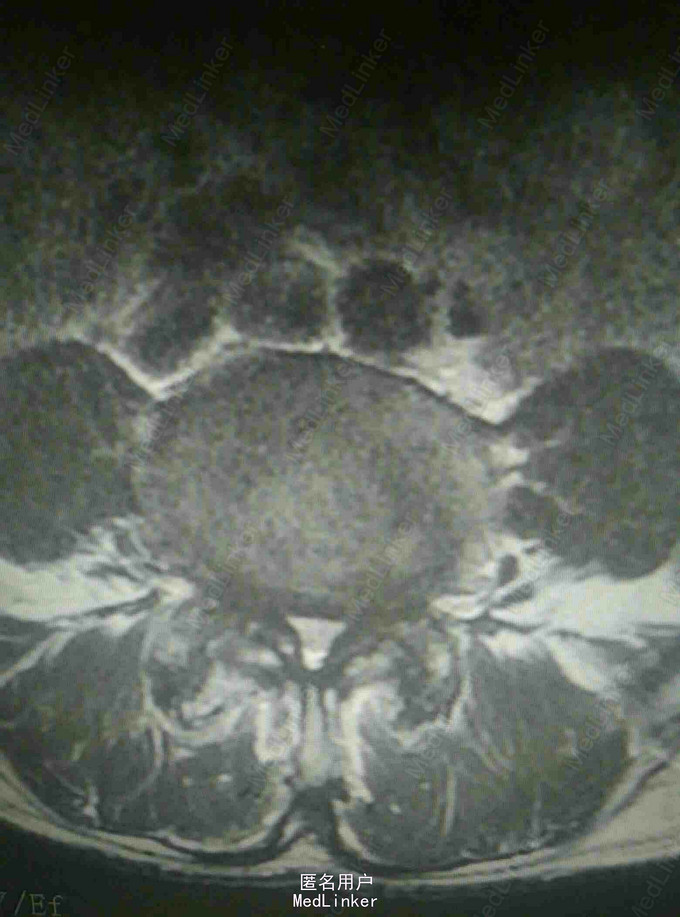

查体:腰4~5棘突及骶部压痛,无明显叩击痛,右大腿外侧疼痛,右足背外侧感觉减退,双下肢肌力正常,双侧直腿抬高实验阴性。 辅查:外院X线片提示腰椎退变 我院核磁提示腰4-5关节突增生内聚,椎间盘后突压迫硬膜囊及神经根

诊断:腰椎管狭窄 治疗:腰椎后路减压植骨内固定术